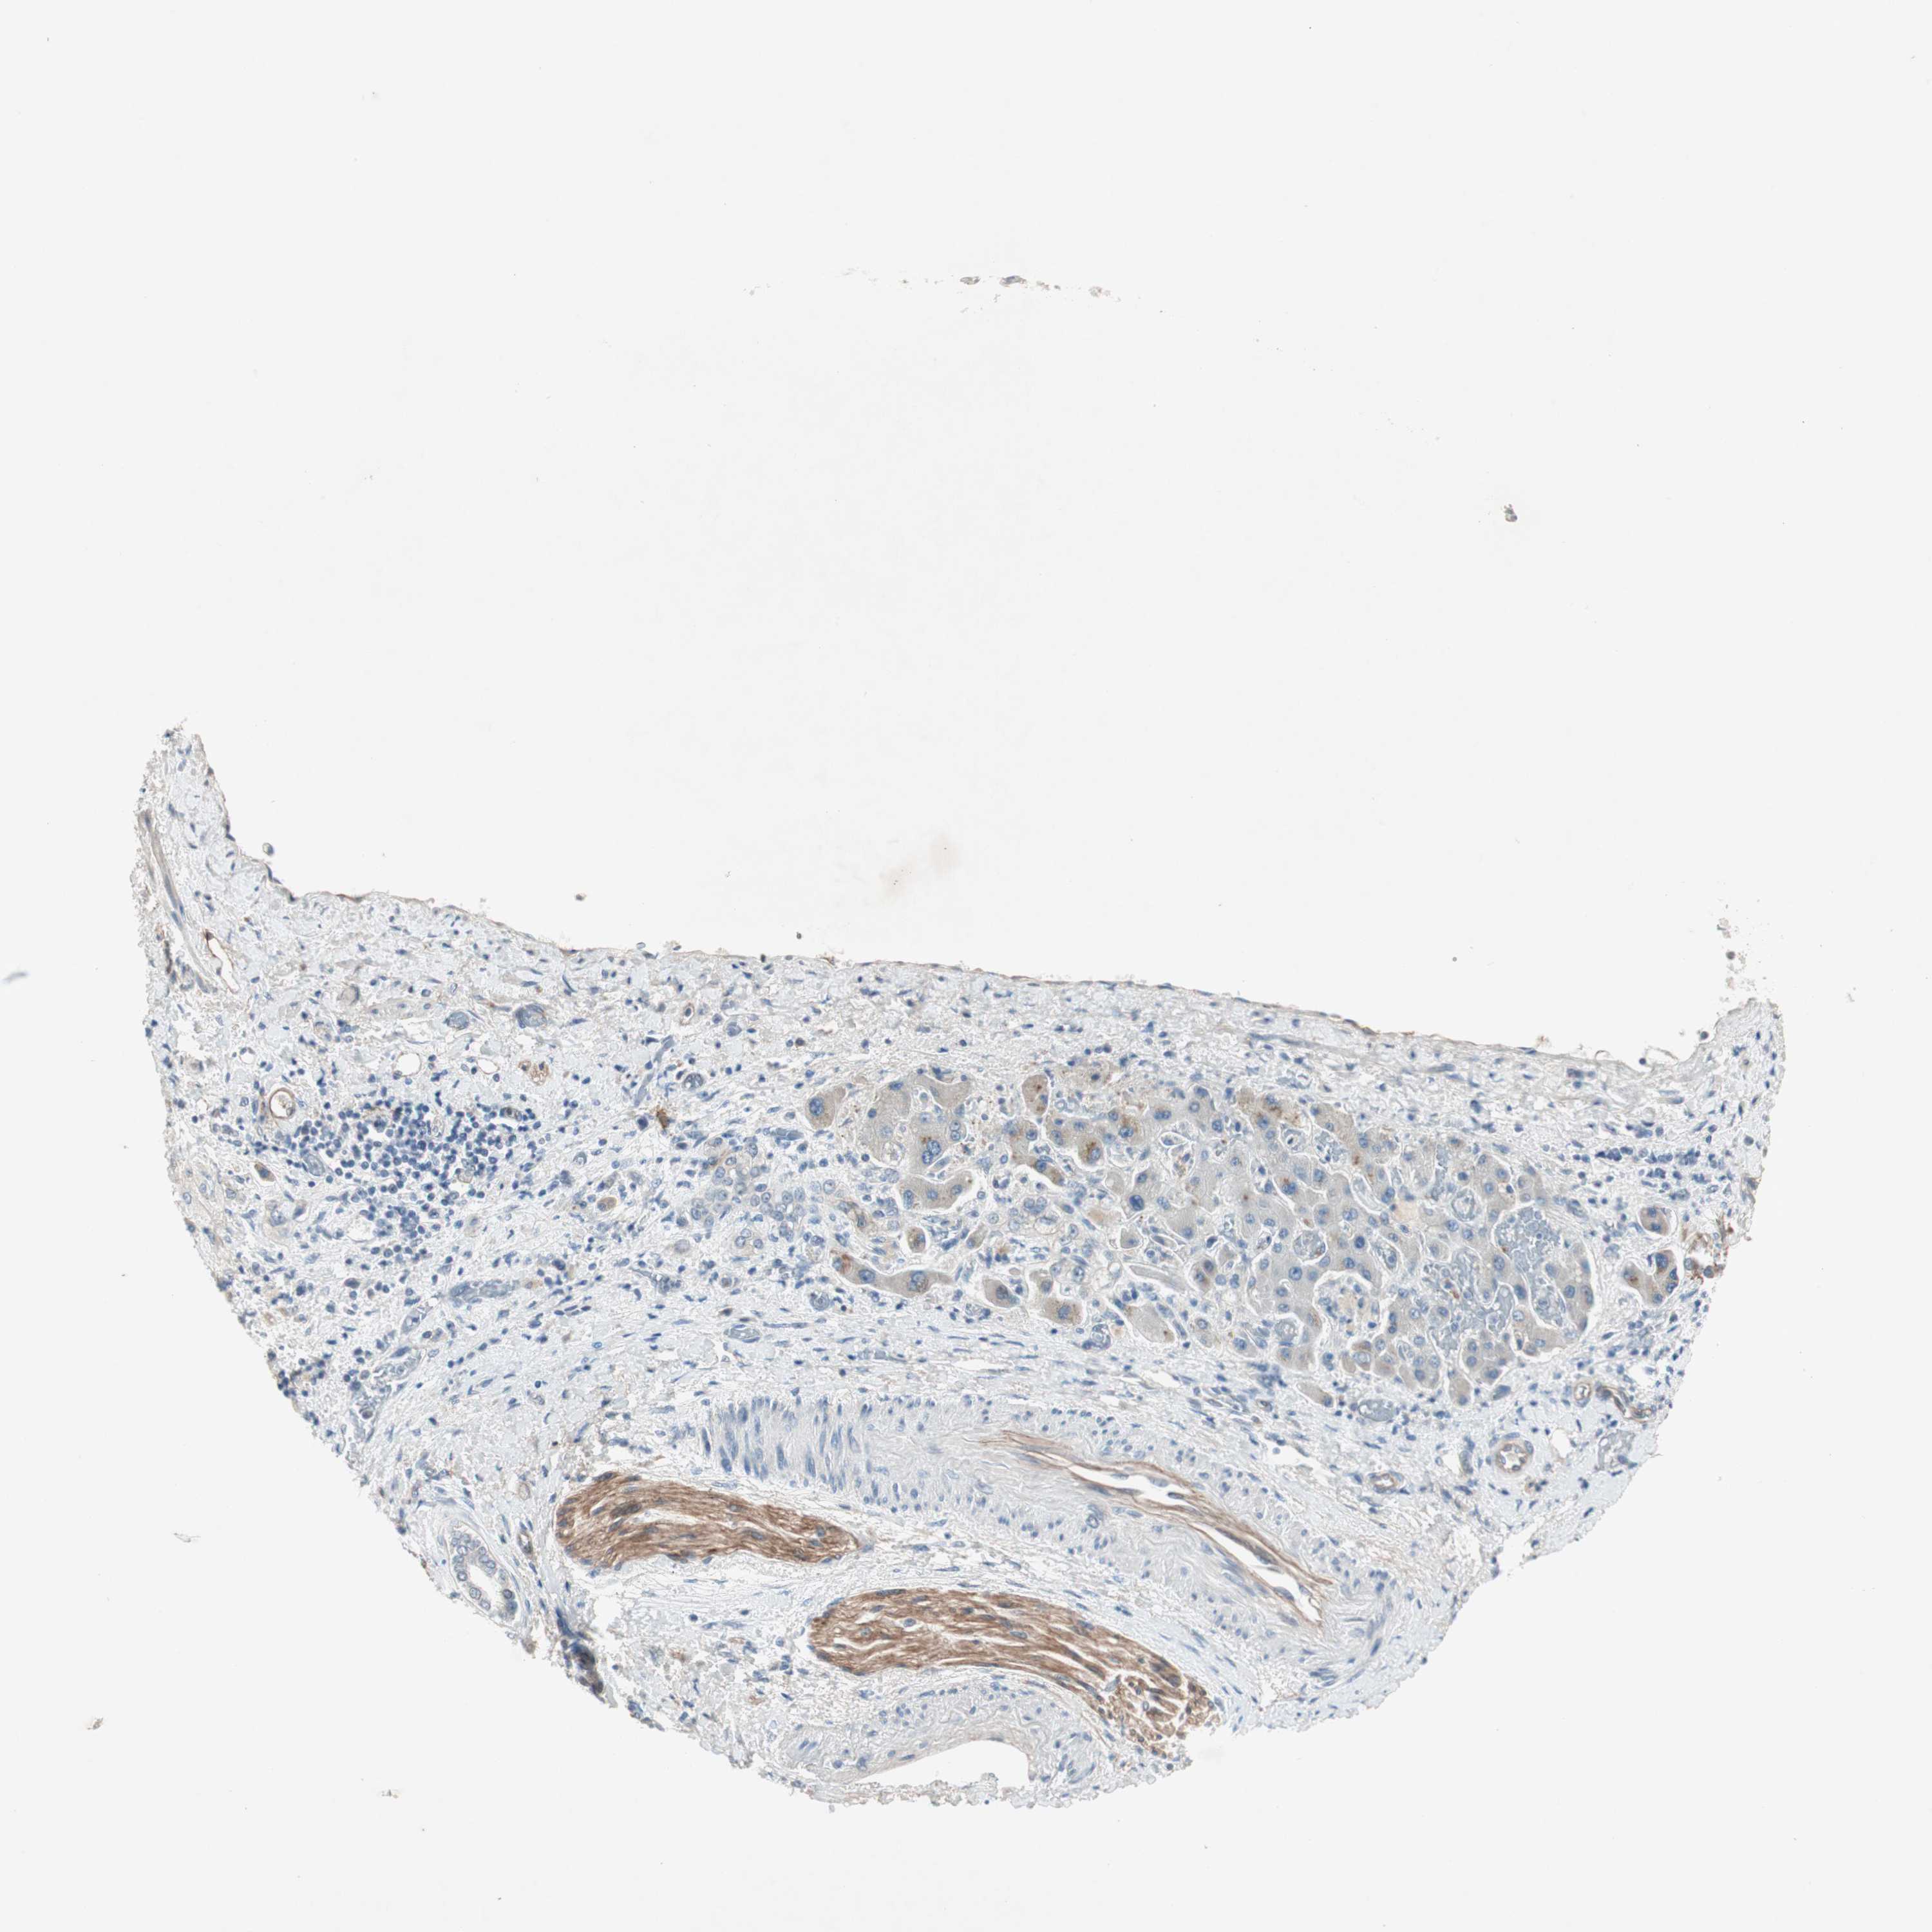

LIVER CANCER - Protein expressioni

A mouse-over function shows sample information and annotation data. Click on an image to view it in a full screen mode. Samples can be filtered based on level of antibody staining by selecting one or several of the following categories: high, medium, low and not detected. The assay and annotation is described here.

Note that samples used for immunohistochemistry by the Human Protein Atlas do not correspond to samples in the TCGA dataset.

Antibody stainingi

Antibody staining in the annotated cell types in the current human tissue is reported as not detected, low, medium, or high, based on conventional immunohistochemistry profiling in selected tissues. This score is based on the combination of the staining intensity and fraction of stained cells.

Each image is clickable and will lead to virtual microscopy that enables deeper exploration of all samples and also displays staining intensity scores, fraction scores and subcellular localization as well as patient and tissue information for each sample.

Antibody HPA036348

Antibody HPA036349

Antibody CAB002422

Antibody CAB005258

Staining

High

Medium

Low

Not detected

Intensity

Strong

Moderate

Weak

Negative

Quantity

>75%

75%-25%

<25%

None

Location

Nuclear

Cytoplasmic/membranous

Cytoplasmic/membranous,nuclear

Cholangiocarcinoma

Carcinoma, Hepatocellular, NOS